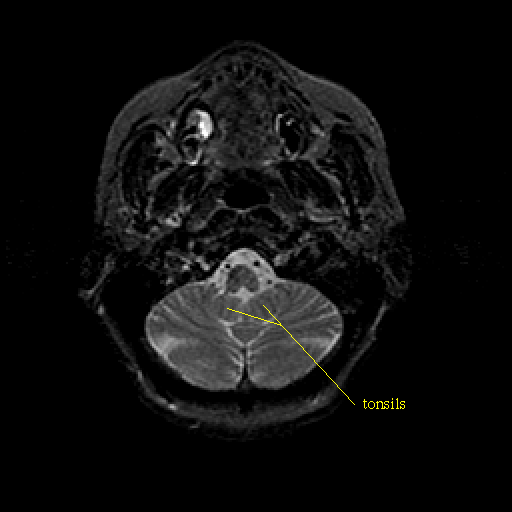

T2-weighted structural MR: Slice 8

Slice 8

Pointers

Labeled